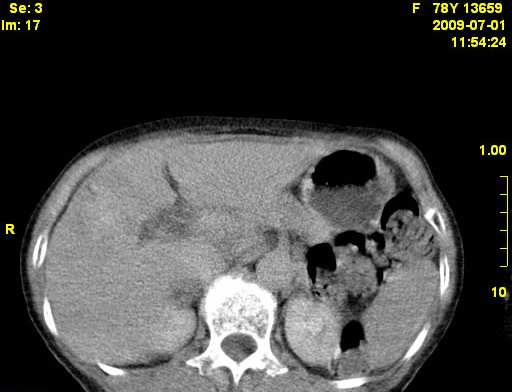

以下是引用zjzjr在2009-7-3 11:02:00的发言:[br]动脉期不均匀强化,门脉期及延迟期强化明显,肝门部见肿大淋巴结影,肝内胆管扩张.考虑肝右叶前段胆管细胞癌伴肝门淋巴结转移,胆内胆管扩张.慢性胆囊炎.

以下是引用dsl555在2009-7-4 10:59:00的发言:[br]考虑肝右叶前段胆管细胞癌伴肝门淋巴结转移,胆内胆管扩张.慢性胆囊炎. [br][br]支持。